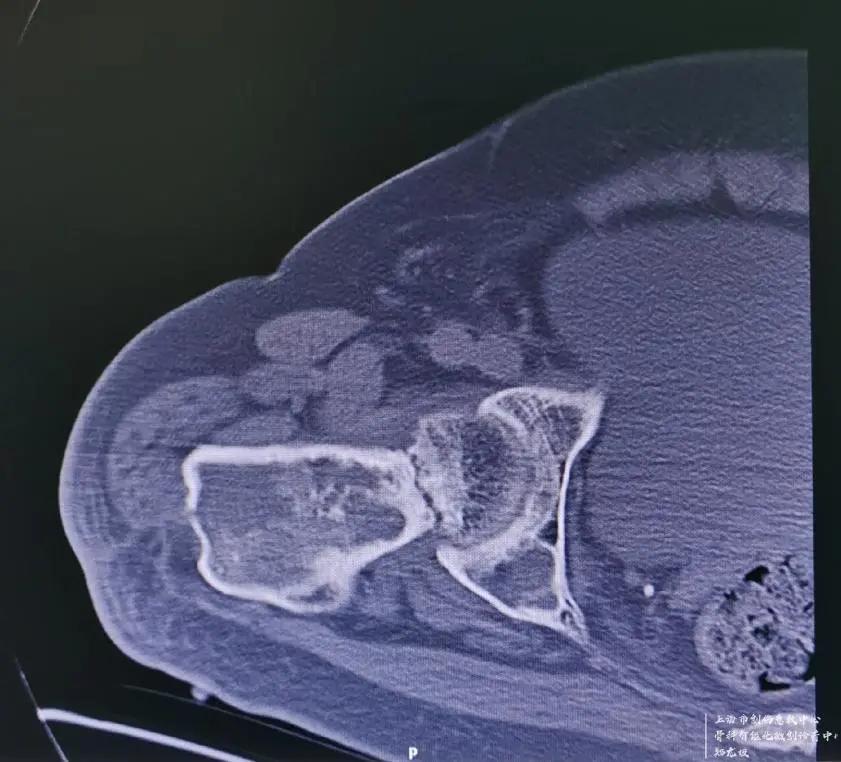

吴先生4岁时就得了右腿股骨的骨纤维结构不良的疾病,这种疾病又叫骨纤维异常增殖症,是先天性非遗传性疾病,主要病理改变是正常骨组织和骨髓被大量增生的纤维组织所替代,在纤维组织内有结构不良的骨小梁。临床上常导致疼痛、畸形、功能障碍及病理骨折,在我国占骨肿瘤样病损的首位。吴先生于1966年不谨慎摔倒后,导致右大腿骨纤维结构不良的部位病理性骨折,行牵引治疗后骨折愈合,后逐渐出现右大腿畸形短缩。

于1985年在某知名医院行右股骨干截骨矫形术,术后出现骨不连,截骨处假关节形成,内固定断裂,大腿畸形短缩进一步加重,左右腿粗细不一,长短相差近15公分,严重地影响了吴先生的正常生活、工作质量。吴先生曾经多次到知名大医院就诊,医生给出的建议是没有更好的治疗办法,也就宣判了吴先生右腿的终生残疾。此次摔倒雪上加霜的是,正好又摔断了畸形一侧大腿的股骨颈,新伤旧患叠加,让吴先生相当绝望!而让吴先生从绝望中起死回生的,是找到了十院骨科创伤中心主任郑龙坡教授------一个擅长啃骨科疑难杂症硬骨头的全国知名中青年专家。

经检查发现,如果是正常发育的大腿骨骼,可以根据骨折类型和患者的年龄不同,采取内固定或人工关节置换的方式进行手术。但由于吴先生右股骨近端骨纤维结构不良伴发严重畸形,且有断裂的内固定钢板存在,无法选择常规的治疗方式进行手术。

针对如此棘手的病例,且上海市血源非常紧张的情况下,郑龙坡教授团队经过充分的术前规划并与家属仔细沟通,决定分期对患者进行手术,一期对肱骨头骨折、肩关节脱位进行手术,二期采取肿瘤型假体置换的方式解决股骨颈骨折、股骨近端骨纤维结构不良伴严重畸形、股骨中段骨不连、内固定断裂等问题。

二期手术面临的最大的问题在于,股骨近端从股骨头至股骨中段骨不连这一段要整个拿掉,创面相对比较大,同时对于患者最关心的患侧肢体短缩15cm的问题,最大程度延长到多长,能否和健康侧一样长且不会导致下肢血管和神经的损伤,是重点考虑的问题。

按照预定计划,患者一期进行了肩部的手术,手术及术后康复锻炼非常顺利。二期股骨手术,先把原来断裂的内固定物取出,再把畸形愈合的股骨近端从骨不连的地方切除,同时切除周围大量增生的骨痂,安装定制的人工股骨近端假体,并重建周围软组织平衡,历经2个小时的奋战,手术顺利完成。